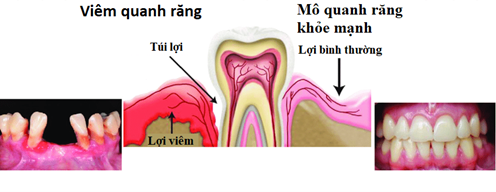

Viêm quanh răng là tình trạng viêm nhiễm xảy ra tại các tổ chức quanh răng như lợi, dây chằng quanh răng, và xương ổ răng. Đây là một phản ứng bảo vệ của cơ thể đối với các tác nhân gây bệnh, thường xuất phát từ việc tích tụ mảng bám và cao răng trong khoang miệng. Nếu không được phát hiện và xử lý kịp thời, viêm quanh răng có thể tiến triển thành các bệnh nha chu nghiêm trọng, gây mất răng và ảnh hưởng đến sức khỏe chung.

Tình trạng viêm nhiễm các tổ chức quanh răng như lợi, dây chằng, xương ổ răng

Trong giai đoạn đầu, viêm quanh răng thường bắt nguồn từ mảng bám và cao răng tích tụ lâu ngày, gây kích thích và viêm nhiễm tại các tổ chức liên quan. Bệnh lý này bắt đầu bằng viêm lợi, sau đó lan rộng ra các dây chằng quanh răng và xương ổ răng, làm suy yếu cấu trúc nâng đỡ của răng.

Khi bệnh tiến triển, các mô liên kết bị phá hủy, dẫn đến tụt lợi, răng dễ lung lay hoặc thậm chí mất răng. Điều đáng lo ngại là quá trình này diễn ra âm thầm, ít có triệu chứng rõ ràng ban đầu, khiến nhiều người chủ quan bỏ qua việc chăm sóc cần thiết.